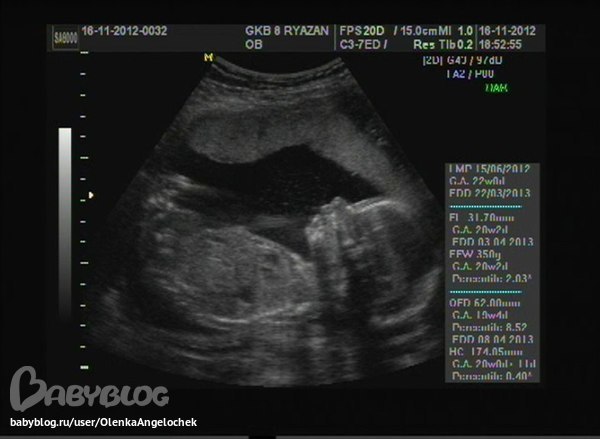

В пятницу, 16 ноября, мы были вместе с мужем на УЗИ. Сидели в очереди с 14:30 до 18.45! В этот день мы ещё ходили на концерт Андрея Бандеры. Опаздывали, надо было успеть к 19 ч. Но УЗИ было для нас намного важнее!)))) Я так тряслась) Я как будто чувствовала, что мне скажут, что у нас будет девочка) Мы же хотели мальчика) А в итоге - растёт красавица - дочка) Здорово! Как только я увидела радость на лице мужа, мне стало намного спокойнее. А ведь это даже и лучше) Доченька... Мы имя уже придумали - Милана.